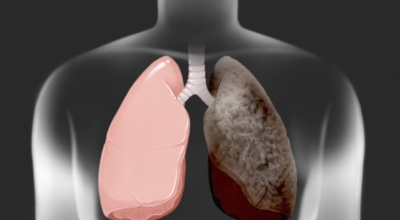

폐암의 공통 위험요소로 손꼽히는 까닭으로 흡연이 있어요. 흡연자는 비흡연자에 비교해 십몇 배는 더 폐암 발병확률이 높다고 하며 어느정도 기간 동안 흡연했는지에 따라 폐암 발생확률은 더욱더 더 높아져요. 흡연자라고 해도 금연을 하게 되면 폐암 발병확률이 가파르게 감소한다고 하니 폐암이 걱정되신다면 가장 먼저 금연은 필수입니다.

간접흡연 외에도 공사장과 같은 곳에서 미세먼지나 석면, 비소, 라돈, 카드뮴 등 신체에 좋지 않은 성분에 노출되는 환경적 요인으로 폐암이 발병할 수 있으며 유전적 요인으로도 폐암이 발병할 수 있다고 해요. 가족 중 폐암을 앓았던 분들이 있다면 그렇지 않은 분들에 비교해 2배 가량 더 폐암에 걸릴 확률이 높다고 하는데요 이렇듯 폐암은 나도 모르는 새에 발병할 수 있으므로 자신의 체력 상태를 수시로 체크하여 폐암을 초기에 발견하는 것이 현명해요.